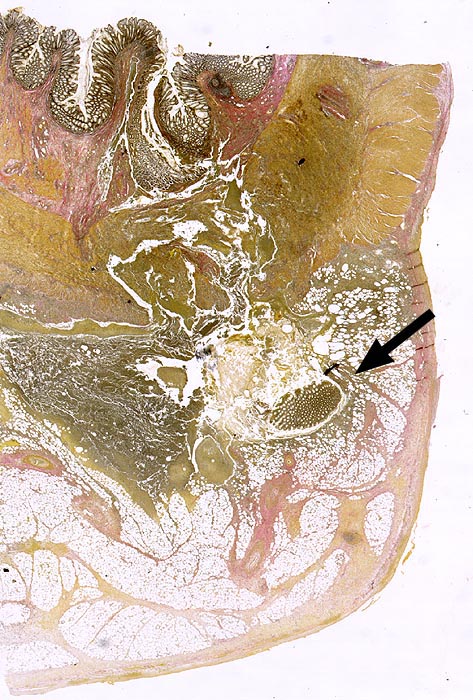

Divertikulitis

Entzündung / Reparatur

Darm, Anus

Kolon Sigma

Virtuelles Präparat

Pathologischer Befund